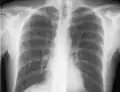

Pneumothorax

The incidence of pneumothorax is highest with subclavian vein catheterization due to its anatomic proximity to the apex of the lung. In the case of catheterization of the internal jugular vein, the risk of pneumothorax is minimized by the use of ultrasound guidance. For experienced clinicians, the incidence of pneumothorax is about 1.5–3.1%. The National Institute for Health and Clinical Excellence (UK) and other medical organizations recommend the routine use of ultrasonography to minimize complications.[5]

If a pneumothorax is suspected, an upright chest x-ray should be obtained. An upright chest x-ray is preferred because free air will migrate to the apex of the lung, where it is easily visualized. Of course, this is not always possible, particularly in critically ill patients in the intensive care unit. Radiographs obtained in the supine position fail to detect 25–50% of pneumothoraces.[6] Instead, bedside ultrasound is a superior method of detection in those too ill to obtain upright imaging.[3]